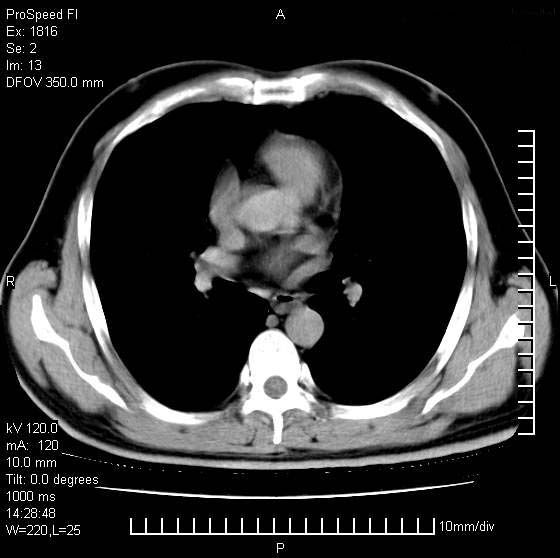

男性,50 ,肺结核9年,咳嗽,胸痛一周。右上肺见一厚壁空洞,周边有点样钙化,胸膜牵拉,洞壁较光整。诊断结核性空洞。有癌性的可能吗? 余肺野无异常,没有上传。

洞壁较厚内壁比较光整,两个病灶有关联性,纵隔淋巴结不大,考虑结核性空洞。

9年的结核应该呈现多形态病灶,该病例只能见到少许纤维索条影,似乎与结核的演变不太相符。空洞内壁不光整,外侧伴有胸膜粘连,考虑癌性空洞可能性大,期待结果。

考虑为右上肺癌。

周围型肺癌不能排除,建议手术治疗。